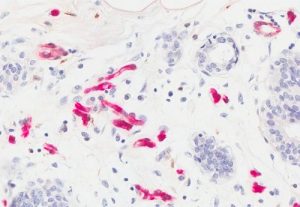

Möglicher Mechanismus für Zusammenhang zwischen Adipositas und Brustkrebs beschrieben13. April 2020 Starke Expression von Fettfettsäurebindungsprotein (FABP4) in Brustdrüsen, rot dargestellt. (Foto: © Universität von Louisville) Es ist allgemein anerkannt, dass höhere Körperfettwerte das Risiko für die Entwicklung von Brustkrebs und anderen Krebsarten erhöhen. Einer aktuellen Veröffentlichung zufolge soll von Fettzellen abgesondertes Protein die Entwicklung von Brustkrebs fördern. In seiner kürzlich veröffentlichen Arbeit berichtet der Mikrobiologe und Immunologe Bing Li vom James Graham Brown Cancer Center an der University of Louisville über diesen von ihm beobachteten Zusammenhang. Li führt seit fünf Jahren vom National Cancer Institute finanzierte Forschungen durch, die ihn auf die Spur einer möglichen Verbindung zwischen der Aktivität eines im Fettgewebe exprimierten Proteins und einer Zunahme in der Entstehung von Brustkrebs führten. In seinem aktuellen Artikel beschreibt Li seine Theorie, dass das Protein FABP4 (fatty acid binding protein), das im Fettgewebe exprimiert wird, für das Wachstum von Tumoren in der Brust verantwortlich ist. „Viele Krebsarten stehen im Zusammenhang mit Fettleibigkeit, nicht nur Brustkrebs“, betont Li. „Mehr als 13 Krebsarten sind eindeutig mit Adipositas verbunden, und ich denke, die Liste wird länger und länger werden, sobald wir mehr Daten haben. In unseren Untersuchung haben wir festgestellt, dass die Fettsäurebindungsprotein-Familie, insbesondere das Mitglied FABP4, eine sehr wichtige Rolle bei der Assoziation von Fettleibigkeit und Krebs spielt, insbesondere Brustkrebs. Wir stellen die Theorie auf, dass FABP4 für den zugrunde liegenden molekularen Mechanismus verantwortlich ist, der die Entwicklung von Brustkrebs im Zusammenhang mit Adipositas fördert.“ Fettgewebe im Körper produziert FABP4 in Fettzellen, wo es wasserunlösliche langkettige Fettsäuren verarbeitet und verteilt. Eine bestimmte Menge FABP4 gelangt unter normalen Bedingungen in den Blutkreislauf. Wenn sich jedoch ein höheres Volumen an Fettgewebe ansammelt, wird mehr FABP4 in den Kreislauf ausgeschieden. „Normalerweise befinden sich diese Moleküle in den Zellen, aber wenn Menschen adipös sind, befinden sich die Moleküle außerhalb“, erklärt Li. Seine Theorie bietet zwei Möglichkeiten, wie FABP4 das Wachstum von Brustkrebstumoren stimulieren kann. Erstens steigt FABP4 innerhalb der Zellen in bestimmten Tumor-assoziierten Makrophagen an. Lis Forschung ergab auch, dass bei Hemmung von FABP4 das Tumorwachstum in Tiermodellen verringert wird, obwohl das Fettgewebe erhalten bleibt. Zweitens fördert das Protein die Entwicklung von Brustkrebs durch direkte Interaktion mit Brustkrebszellen, wenn erhöhte FABP4-Spiegel bei Fettleibigkeit außerhalb der Fettzellen zirkulieren. In der Versuchen an Tieren waren die Entwicklung und das Wachstum von Brusttumoren bei adipösen Tieren, bei denen FABP4 unter Kontrolle war, verringert. Darüber hinaus scheint FABP4 im Blutkreislauf in mehreren Mechanismen zu wirken, die Wechselwirkungen zwischen Tumorkomponenten und Fettzellen und dadurch die Krebsentwicklung fördern. Darüber hinaus hat Lis Forschungsgruppe kürzlich Ergebnisse veröffentlicht, die zeigen, dass verschiedene Arten fettreicher Ernährung unterschiedliche Auswirkungen auf die Tumorentwicklung haben. Eine fettreichen Ernährung, die viel Kakaobutter oder Fischöl enthält, führt zu fettbedingter Adipositas. Die Ernährung mit viel Kakaobutter hat jedoch ein erhöhtes Wachstum von Brusttumoren zur Folge, während dies bei einer Ernährung, die viel Fischöl beinhaltet, nicht der Fall ist. Diese Studie bestätigt laut ihren Autoren nicht nur die entscheidende Rolle von FABP4 bei mit Fettleibigkeit assoziiertem Krebs, sondern zeigt auch, dass nicht jede Fettleibigkeit die Entwicklung von Tumoren fördert. Li und sein Team glauben, dass ein besseres Verständnis der Wirkungsweise von FABP4 sowohl in Makrophagen als auch im Blutkreislauf Möglichkeiten bieten könnte, das Voranschreiten bestimmter Brustkrebsarten zu verhindern. Es könne auch zur Entwicklung von Behandlungsmethoden führen, die auf FABP4 mit Arzneimitteln oder spezifischen Antikörpern abzielen. „Jetzt versuchen wir, einige Antikörper für dieses Protein zu generieren, was eine sehr effektive Therapiestrategie für Krebs im Zusammenhang mit Fettleibigkeit sein könnte“, sagt Li.